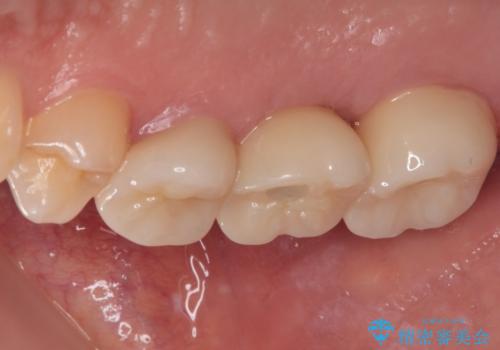

壊れやすいブリッジ インプラント治療で安定した咬み合わせに

- 頻繁に脱離を繰り返す奥歯のブリッジが欠けてしまったとのことで来院された患者様です。

外科処置を回避するためにブリッジ治療を選択されたそうですが、頻繁に脱離するので、欠けた部分のクラウンの作り替えと、欠損部のインプラント治療を行うこととしました。

最後方歯は、クラウンを維持するための高さが不足していたため、インプラント処置の際に歯冠長を延長する手術を併用し、維持力を増すこととしました。

上顎洞までの骨高さが低いケースでしたが、ショートインプラントと骨圧縮機能を持つドリルの使用により、上顎洞底挙上を行うことなく、インプラント治療を行うことができました。